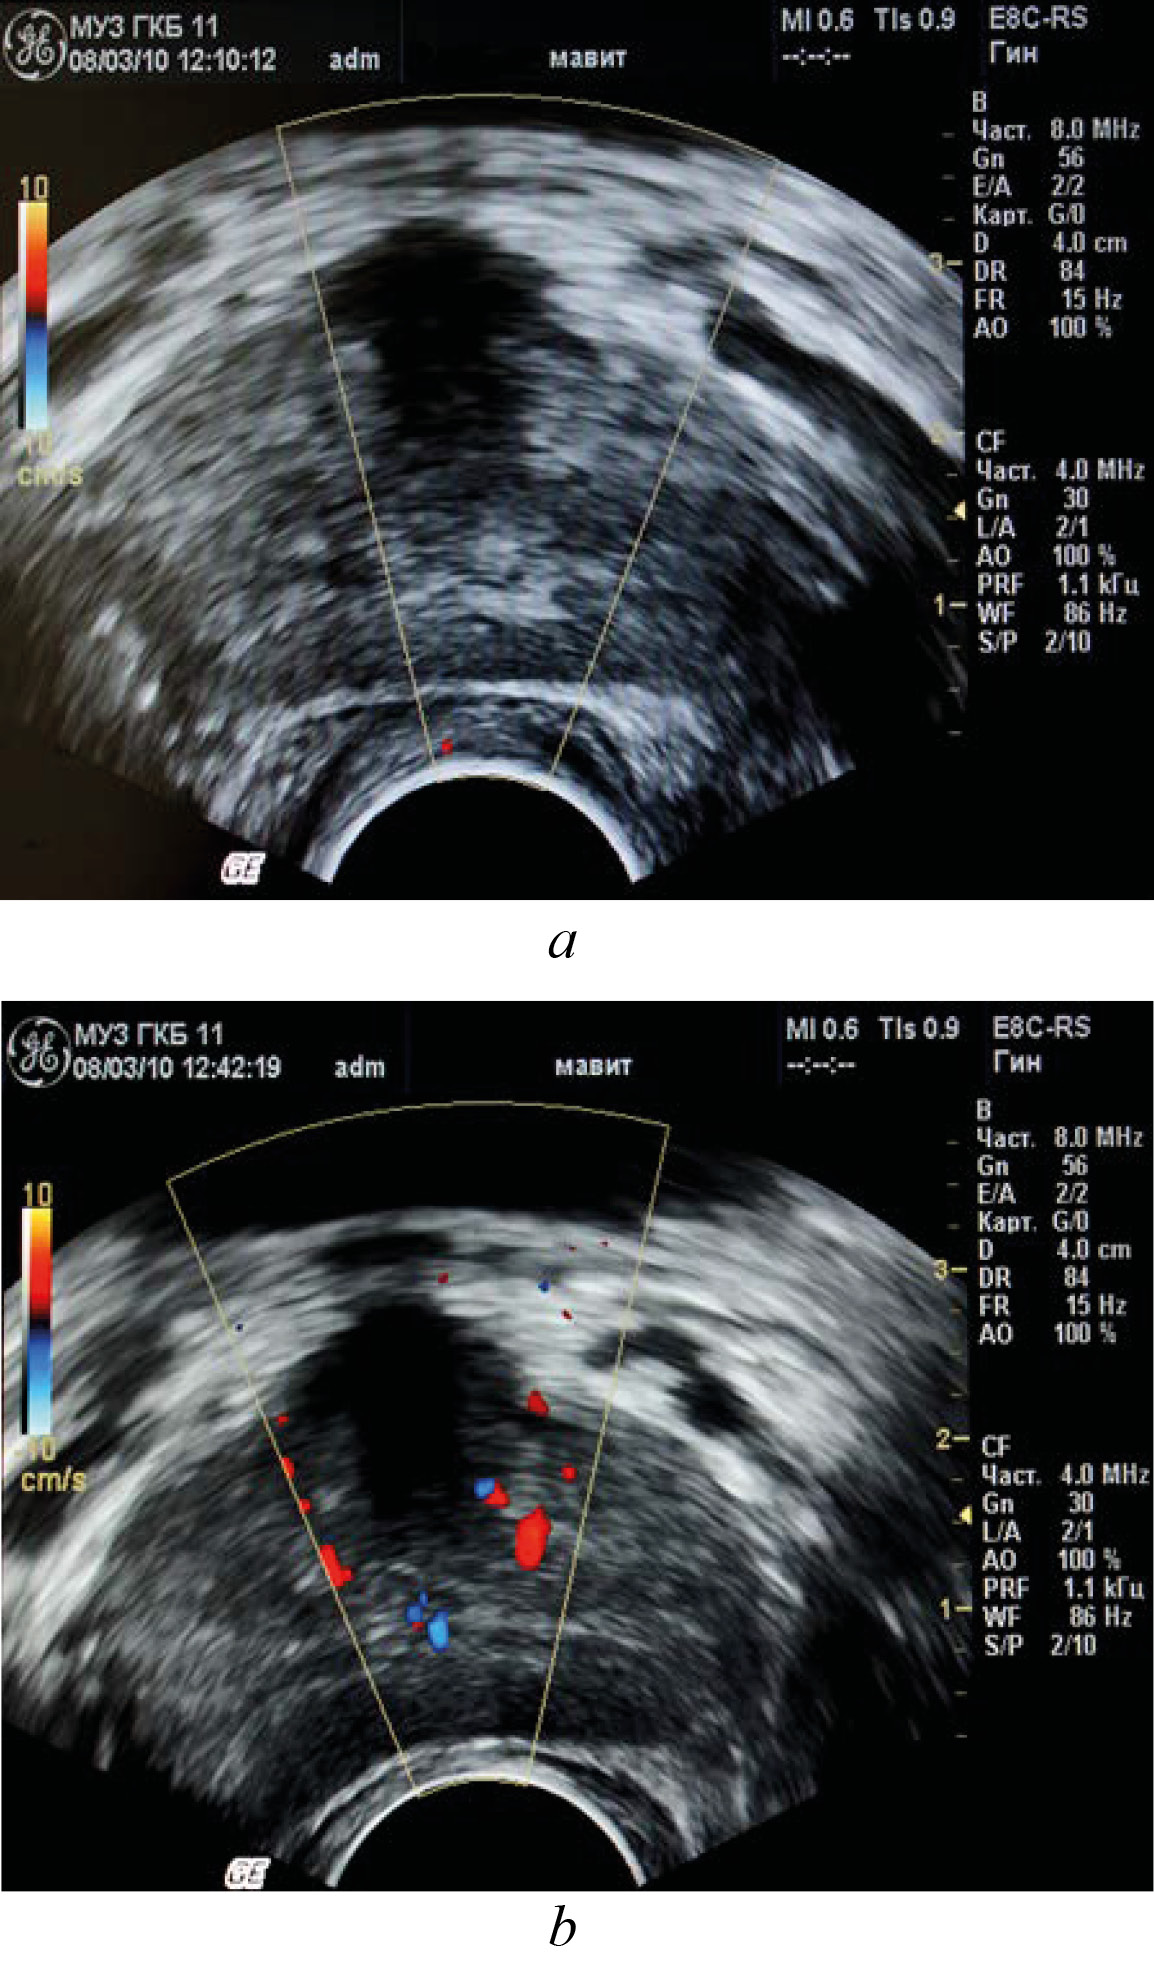

To evaluate prostatic blood flow after a local physiotherapy treatment using the MAVIT device, 10 patients had transrectal (color Doppler mapping) ultrasound of the prostate before and after the treatment, which showed improved microcirculation in the prostate tissue. MAVIT therapy resulted in a pronounced reaction of improved circulation throughout the vascular basin (see Fig. 3). The average linear peak velocity in the studied subgroup increased by 1.1 times and the resistance index decreased by 1.2 times compared to the baseline. The average vascular density increased by more than 2.5 times.

Fig. 3. Dopplerogram of the prostate before (a) and after (b) the session of physiotherapy on the device MAVIT.